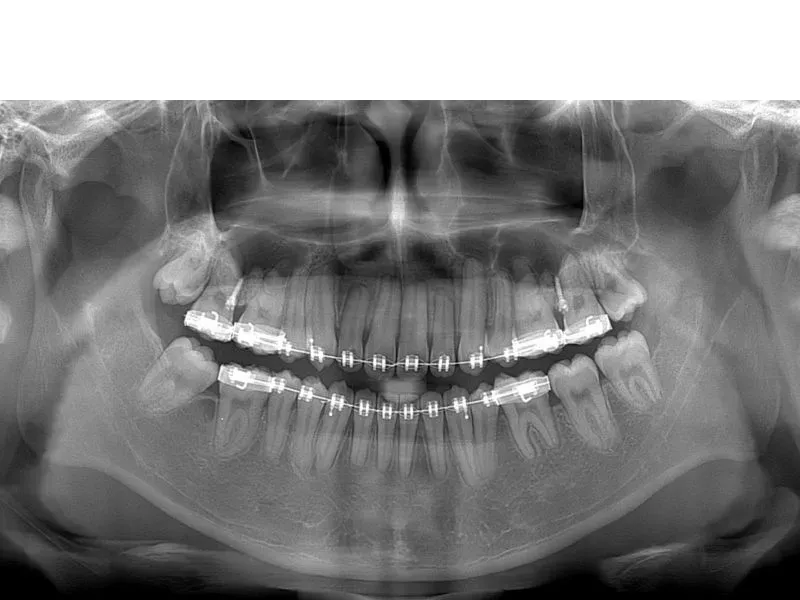

Một chiếc X-quang toàn hàm sẽ không chiếm quá nhiều diện tích trong phòng khám nha khoa. Do đó, bác sĩ có thể dễ dàng sắp xếp một phòng chì đủ đặt vừa chiếc máy. Với thiết kế sang trọng và nhỏ gọn, máy X-quang Pano IC5 HD Morita được đặt vừa xinh trong diện tích 2m2.

Hình ảnh chụp bởi thiết bị X-quang cận chóp sẽ bị giới hạn trong 3-4 răng. Nếu bệnh nhân có tổn thương ở những chiếc răng khác không thuộc khu vực chụp, bác sĩ sẽ bỏ lỡ bệnh lý – chính là bỏ lỡ doanh thu của mình.

Khi bác sĩ khai thác được càng nhiều vấn đề dựa trên một tấm phim toàn hàm rõ nét, phòng khám sẽ tăng doanh thu từ mỗi bệnh nhân ghé thăm. Đây là điều mà mọi chiếc máy X-quang cận chóp không làm được.